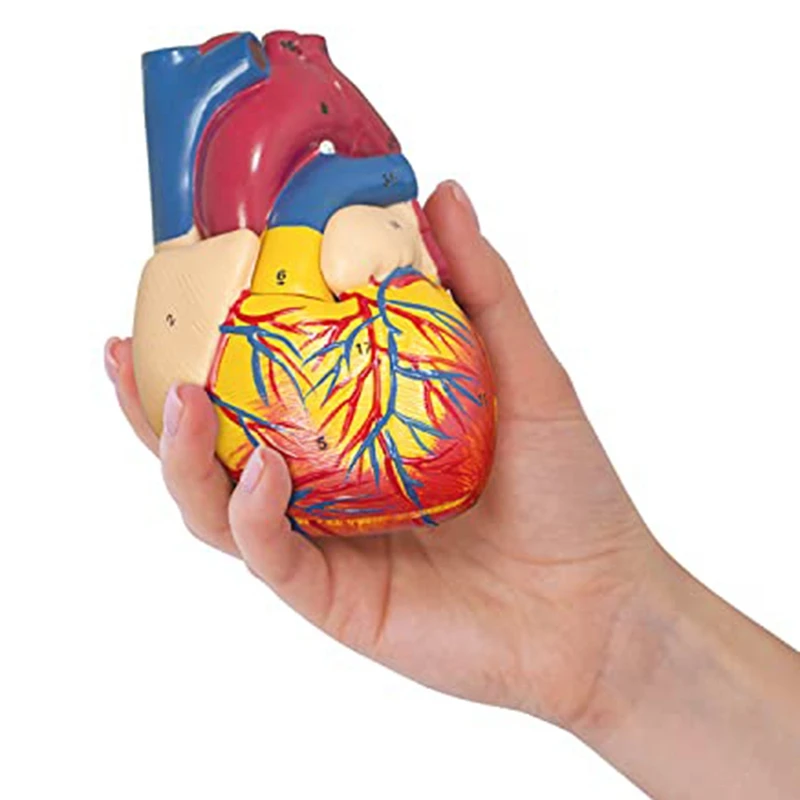

Фотографии и 3D-модели анатомии сердца человека